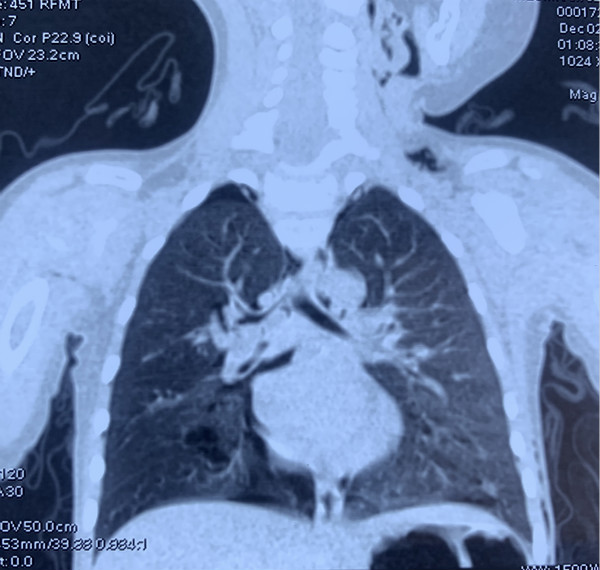

前不久,耳鼻咽喉头颈外科病院急诊收治一名外地转来的22月龄小男婴,据患儿家人讲,患儿2天前玩耍时突然出现哭闹,口唇发紫,气喘,夜间烦躁,不能入睡。在当地医院经抢救后检查胸部CT,提示气管隆突分叉处、左主支气管内异物;纵隔、颈部皮下多发积气,双侧少量气胸,考虑气管穿通伤。由于当地医疗技术及条件限制,患儿被紧急送往西安交大二附院救治。

耳鼻咽喉头颈外科病院接诊时,发现患儿精神差,口唇发紫,哭闹时伴有明显气促、喘息,听诊双肺干湿性啰音,右肺呼吸音低。家属无法提供准确异物误吸情况。值班医师接诊后结合患儿病史、体征及影像学检查结果,基本确诊“呼吸道异物、纵隔气肿、呼吸困难”,在行体格检查时,发现听诊与当地CT检查结果不符,重新做支气管CT三维重建扫描发现右主支气管有异物,说明异物在气管内存在移位、活动,这会加重呼吸困难,并随时会出现窒息,造成气管进一步损伤的风险也会增加。